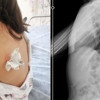

Sırtından kanlar akan küçük kızın yorgun mermiyle vurulduğu anlaşıldı. Anne Ergün, kızını hemen Adana Şehir Eğitim ve Araştırma Hastanesi’ne götürdü. Meliha Beray, sırtındaki kurşunun ameliyatla çıkarılmasının ardından yoğun bakıma alındı.